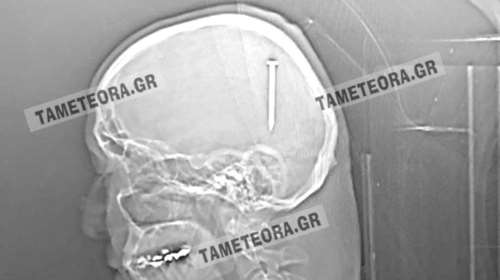

Απίστευτο: Καρφί 5 εκατοστών σφηνώθηκε στο κεφάλι άνδρα στην Καλαμπάκα [εικόνες]

Από θαύμα ζει ένας ένας κάτοικος της Καλαμπάκας, καθώς βρέθηκε ξαφνικά με ένα καρφί 5 εκατοστών σφηνωμένο στο κεφάλι του.